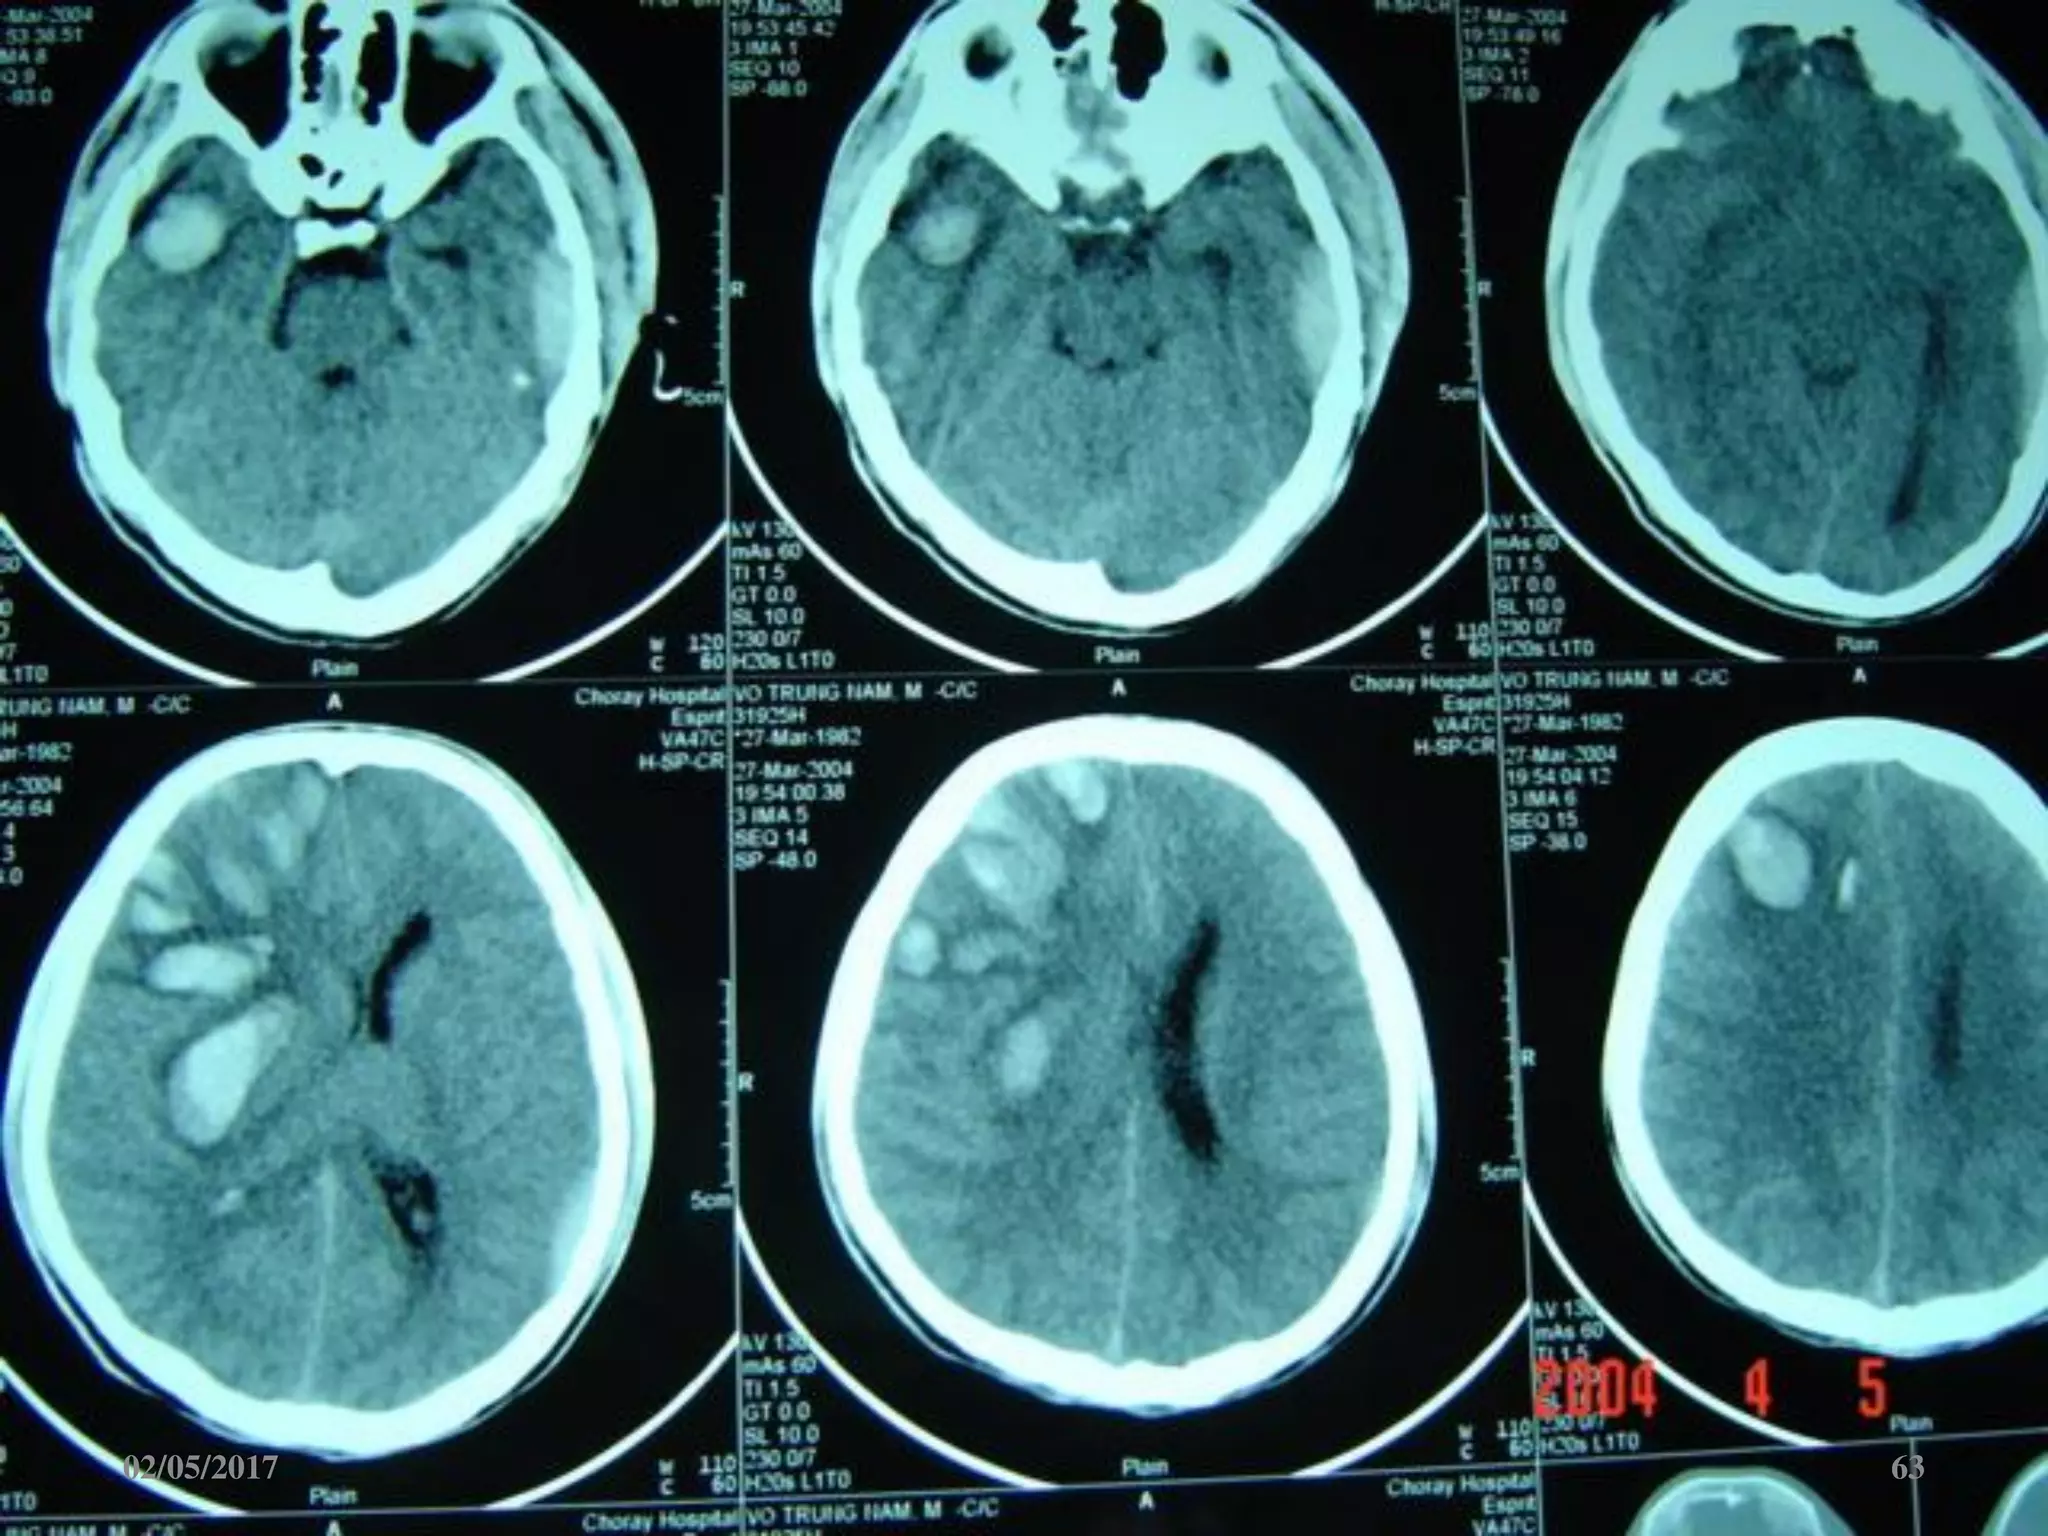

Máu tụ trong não

• Vị trí: trán, thái

dương, đỉnh, chẩm.

• Hình ảnh tăng đậm

độ trong tổ chức não

02/05/2017 63